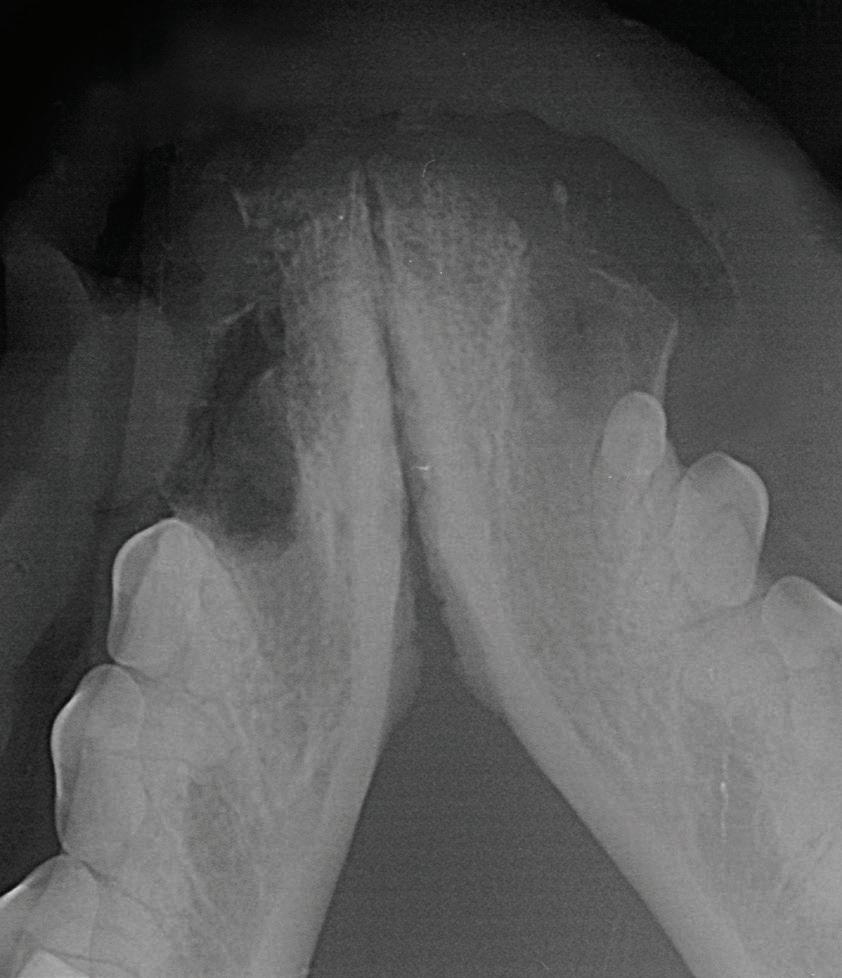

With 10 adjustable power settings and different sized veterinary specific tips, the iM3 Vet-Tome is suitable for small cats to large dogs, and even lions.

See the side-by-side difference between using the iM3 VetTome, compared to hand instruments only.

Tooth 304 was extracted using the iM3 Vet-Tome and as you can see the labial plate of bone is intact.